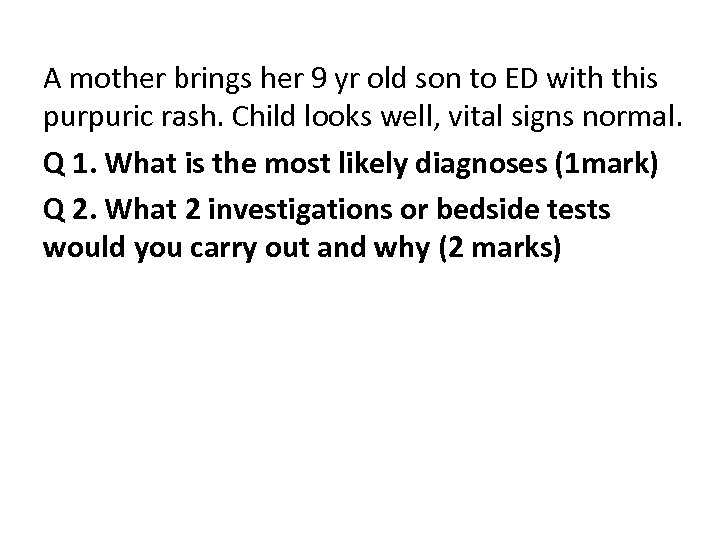

A mother brings her 9 yr old son to ED with this purpuric rash. Child looks well, vital signs normal. Q 1. What is the most likely diagnoses (1 mark) Q 2. What 2 investigations or bedside tests would you carry out and why (2 marks)

A mother brings her 9 yr old son to ED with this purpuric rash. Child looks well, vital signs normal. Q 1. What is the most likely diagnoses (1 mark) HSP Q 2. What 2 investigations or bedside tests would you carry out and why (2 marks) • • • Normal urine analysis – no haematuria or proteinuria or for blood & protein FBC - not ITP leukaemia infection Normal coagulation screen – not clotting problem factor deficiency Normal electrolytes – no renal involvement Normal BP – for renal involvement